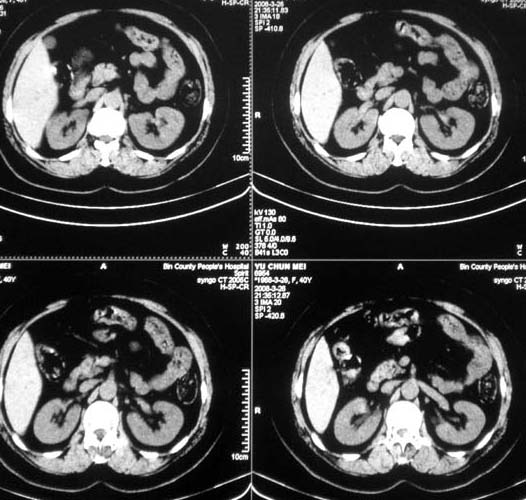

肝内多发占位性病变;建议:行ct增强检查。

增强后再说。

肝内占位性病变:肝血管瘤可能性大,建议必须增强扫描。

增强后在讨论